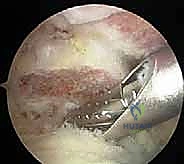

3. استكشاف المفصل وإزالة الأنسجة الملتهبة (Diagnostic Arthroscopy & Bursectomy):

قبل الوصول للترقوة، يقوم الجراح بفحص شامل لمفصل الكتف الداخلي (Glenohumeral joint) والحيز تحت الأخرم (Subacromial space). يتم استخدام جهاز الكي الحراري (Radiofrequency wand) لإزالة الجراب الملتهب (Bursa) والأنسجة الليفية المتندبة التي تسبب الألم.

4. الاستئصال العظمي الدقيق (Bone Resection - The Mumford Procedure):

هنا تتجلى خبرة الجراح. الهدف هو إزالة جزء صغير جداً من نهاية عظم الترقوة (الطرف البعيد).

* يتم استخدام أداة قطع عظمية دقيقة جداً (Arthroscopic Burr).

* الكمية المستأصلة حاسمة: يقوم الدكتور هطيف بإزالة حوالي 5 إلى 8 ملليمترات فقط من العظم. إزالة كمية أقل قد لا تحل مشكلة الاحتكاك، وإزالة كمية أكبر (أكثر من 10 ملم) قد تؤدي إلى عدم استقرار المفصل وتضرر الأربطة الغرابية الترقوية (CC ligaments) الحيوية. الدقة هنا تقاس بالملليمتر.

* يتم تشكيل نهاية العظم المتبقية لتكون ناعمة ومسطحة، مع التأكد من إزالة جميع النتوءات العظمية العلوية والخلفية لمنع أي احتكاك مستقبلي.